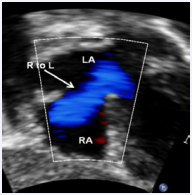

Figure 6 Selected video frame from subcostal view of a neonate with tricuspid atresia demonstrating right-to-left (R to L) shunt (arrow) across the interatrial communication. LA, Left atrium; RA, Right atrium [36].

Figure 6: Selected video frame from subcostal view of a neonate with tricuspid atresia demonstrating right-to-left (R to L) shunt (arrow) across the interatrial communication. LA, Left atrium; RA, Right atrium [36].

Echo-Doppler studies are also useful in demonstrating an ASD/PFO with a right-to-left shunt (Figure 6) and a VSD with a left-to-right shunt (Figure 7).